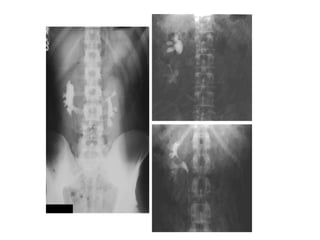

X-QUANG HỆ NIỆU

KUB

• Mục đích:

Đánh giá vôi hóa bất thường của hệ

niệu

Đánh giá tình trạng ổ bụng

Bất thường hệ thống xương

—Kỹ thuật:

Chuẩn bị bệnh nhân:

Tư thế BN : nằm ngửa, phim chụp AP

Yêu cầu: lấy từ cực trên thận đến hết

khớp mu.

• Phân tích kết quả:

- Thận

- Bất thường đậm độ

đường niệu

- Dải mỡ cơ thắt lưng

chậu

- Tình trạng ổ bụng

- Hệ thống xương

• Hạn chế:

- Độ nhạy và độ đặc hiệu phát

hiện sỏi hệ niệu không cao ( ≤

60%) do : sỏi nhỏ, sỏi không cản

quang, trùng lắp vào xương…

- Cần phân biệt với nhiều

nguyên nhân vôi hóa khác trong

ổ bụng ( Vôi hóa TM chậu:

Phlebolith,…)